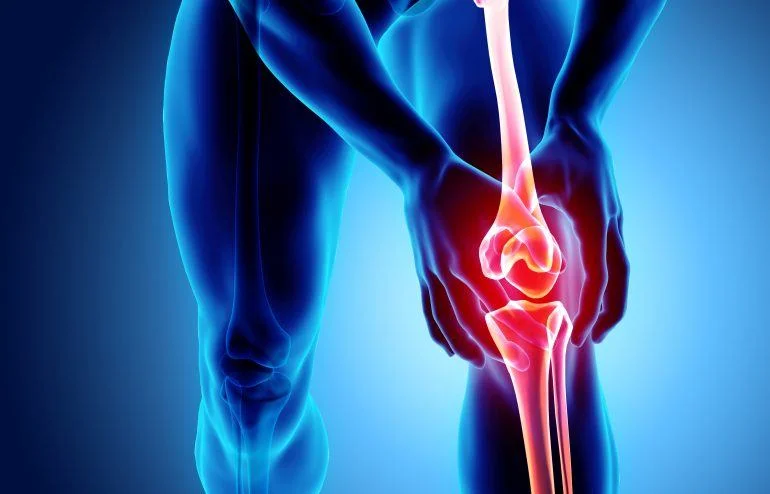

Your knees are among the strongest and most complex joints in your body—and also among the most vulnerable. Whether it’s a sharp pain when climbing stairs, stiffness after sitting, or a persistent ache that limits your activity, knee pain can dramatically impact your daily life.

Knee pain can come from many sources. Understanding the root cause is essential for effective, lasting relief. Common conditions include:

Osteoarthritis: Gradual wear-and-tear of knee joint cartilage

Ligament Injuries: Sprains or tears (such as ACL or MCL injuries)

Meniscus Tears: Damage to the cartilage that cushions your knee

Tendinitis: Inflammation from overuse, often called “jumper’s knee”

Patellofemoral Pain Syndrome: Pain around the kneecap, common in athletes